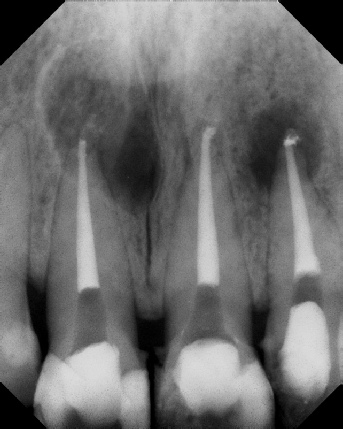

COMPLICATED ANATOMY LARGE LESIONS CALCIFIED CANALS PERFORATION / RESORPTION SEPARATED INSTRUMENTS SURGICAL CASES RETREATMENT / pOST REMOVAL OPEN APICES ACCESS THRU CROWNS Root Canal Case Portfolio